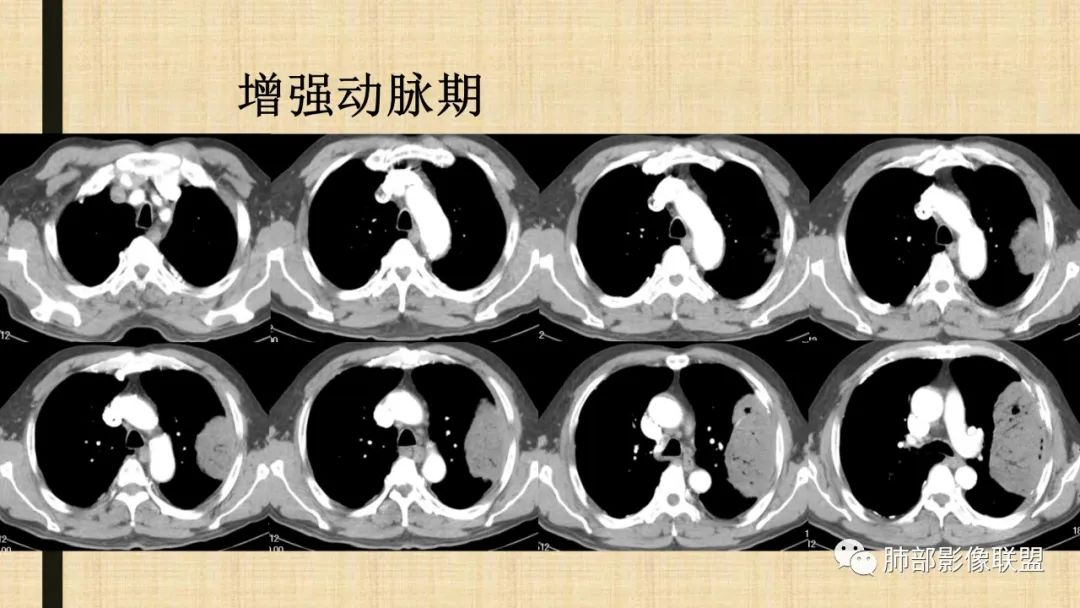

老年男性,糖尿病病史,消瘦、乏力三个月,影像表现左肺上叶胸膜下团块,有一定张力,内部疏松,可见支气管影及坏死区,增强病灶边缘环形强化,内部未见强化,考虑炎性肉芽肿病变,隐球?奴卡?放线菌?鉴别淋巴瘤。

增强没有强化,血管束正常,气管束有正常有扩张,内有空洞,考虑炎性病变,隐球?

支持淋巴瘤,左上肺大肿块,有分叶,边缘光整,病灶内密度不均,可见支气管扩张征,增强后可见血管影征。周围肺野清晰。

左肺上叶肿块,宽基底与胸膜相连,跨叶裂,边缘清晰膨隆,可见小分叶,其内支气管充气,部分扩张、僵直,呈枯枝征,支气管达边征,增强无明显强化,可见血管造影征,考虑恶性病变,淋巴瘤,鉴别粘液腺癌。

我要修正一下观点了:仔细看了视频,肿块占位效应明显,对周围血管,支气管有推挤,增强后强化不明显,NSE增高,半年体重下降25公斤,虽然有内部支气管扩张,血管漂浮,边界清楚支持淋巴瘤,但强化太低,膨隆,占位推挤太明显(淋巴瘤一般没有这么明显的占位效应),胸膜关系有载桩,恶病质明显(乏力,半年体重下降了25公斤),NSE也明显增高,就不支持淋巴瘤了。还是考虑外朝内的恶性肿瘤,间质来源的肉瘤伴有神经内分泌分化或者大神泌。

不支持淋巴瘤的有四点:1、对周围血管支气管推挤明显。2、胸膜有栽桩,3、强化太弱(淋巴瘤一般还是中度以上甚至高度强化多见),4、NSE升高明显,体重下降太明显。

5)肿瘤强化方式:肺部恶性肿瘤强化程度与其血供丰富程度相关,血供丰富多强化明显,反之则较差。由于PSC 周边实性部分富血供及内部黏液变性、坏死,增强后肿块多数呈轻-中度边缘环形强化或不均匀小斑片状强化。国外学者对照病理发现肿瘤细胞或胶原组织增强扫描时强化,无强化的低密度区代表了黏液样变性区和出血坏死区。